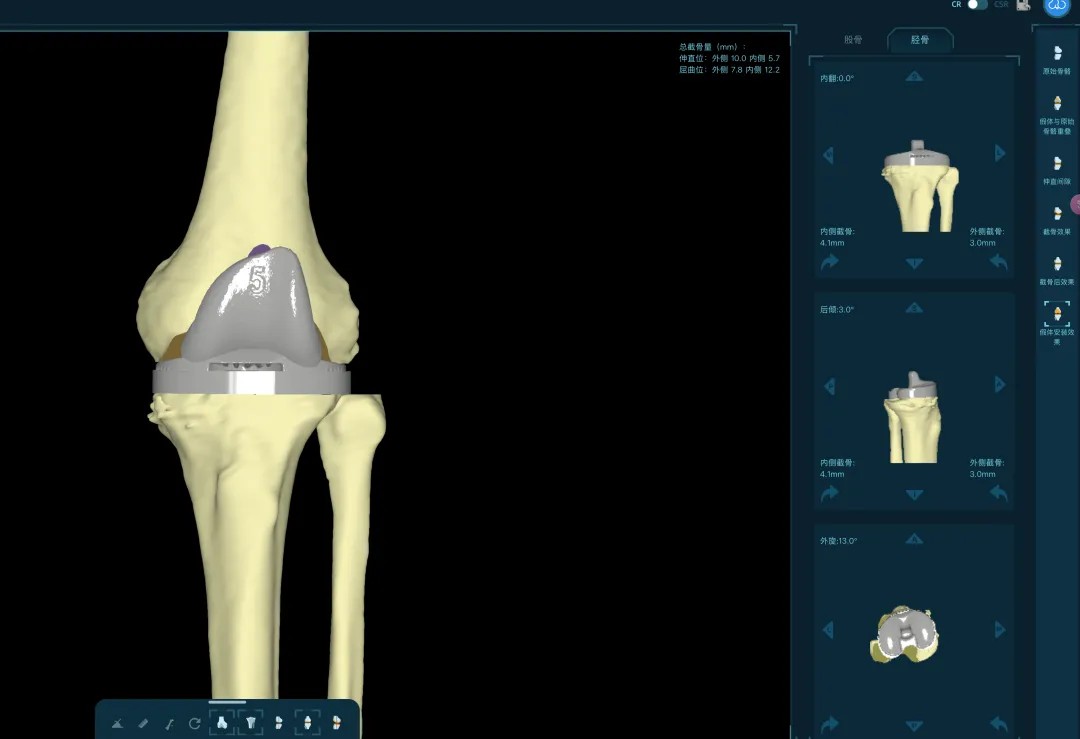

清創(chuàng)只是第一步,如何在一片“復(fù)雜地形”中重建一個(gè)穩(wěn)定、功能良好的膝關(guān)節(jié),是更大的挑戰(zhàn)。為此,團(tuán)隊(duì)引入了計(jì)算機(jī)輔助手術(shù)規(guī)劃系統(tǒng)。

通過(guò)患者的CT數(shù)據(jù),系統(tǒng)構(gòu)建出膝關(guān)節(jié)的三維數(shù)字模型,精確評(píng)估骨缺損的范圍與形態(tài)。醫(yī)生可以在虛擬空間中,提前模擬手術(shù)過(guò)程,為患者“量體裁衣”,規(guī)劃出假體安放的最佳位置、角度以及所需填充骨缺損的特殊墊塊型號(hào)。

“這相當(dāng)于在真實(shí)戰(zhàn)斗前,進(jìn)行了一次全方位的沙盤(pán)推演。”羅軍介紹,這種規(guī)劃確保了手術(shù)的精準(zhǔn)度,縮短了手術(shù)時(shí)間,也為使用先進(jìn)的翻修假體系統(tǒng)做好了完美鋪墊。

本次手術(shù)的核心,是采用了Evolution® ECCK膝關(guān)節(jié)翻修系統(tǒng)。該系統(tǒng)專為應(yīng)對(duì)翻修手術(shù)中常見(jiàn)的嚴(yán)重骨缺損、韌帶功能不全等極端復(fù)雜情況而設(shè)計(jì)。

其模塊化的組件提供了前所未有的靈活性,就像一套高精度的“工程套件”,允許醫(yī)生在術(shù)中根據(jù)實(shí)際骨缺損情況,自由組合不同尺寸的墊塊、延長(zhǎng)桿等部件,實(shí)現(xiàn)關(guān)節(jié)線和力學(xué)穩(wěn)定性的個(gè)體化重建。